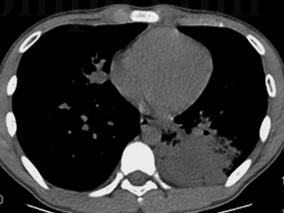

1小时条评论一、病史摘要 患者,男性,39岁,农民。因反复咯血3年,再发加重3周于2008年11月17日入院。患者自诉于3年前无明显诱因出现间断咯血,量不多,一日约10ml左右,鲜红色,伴干咳,胸痛,气促,无发热、盗汗、体重减轻等。2006年9月无明显诱因出现咯鲜血,一次约500ml。...